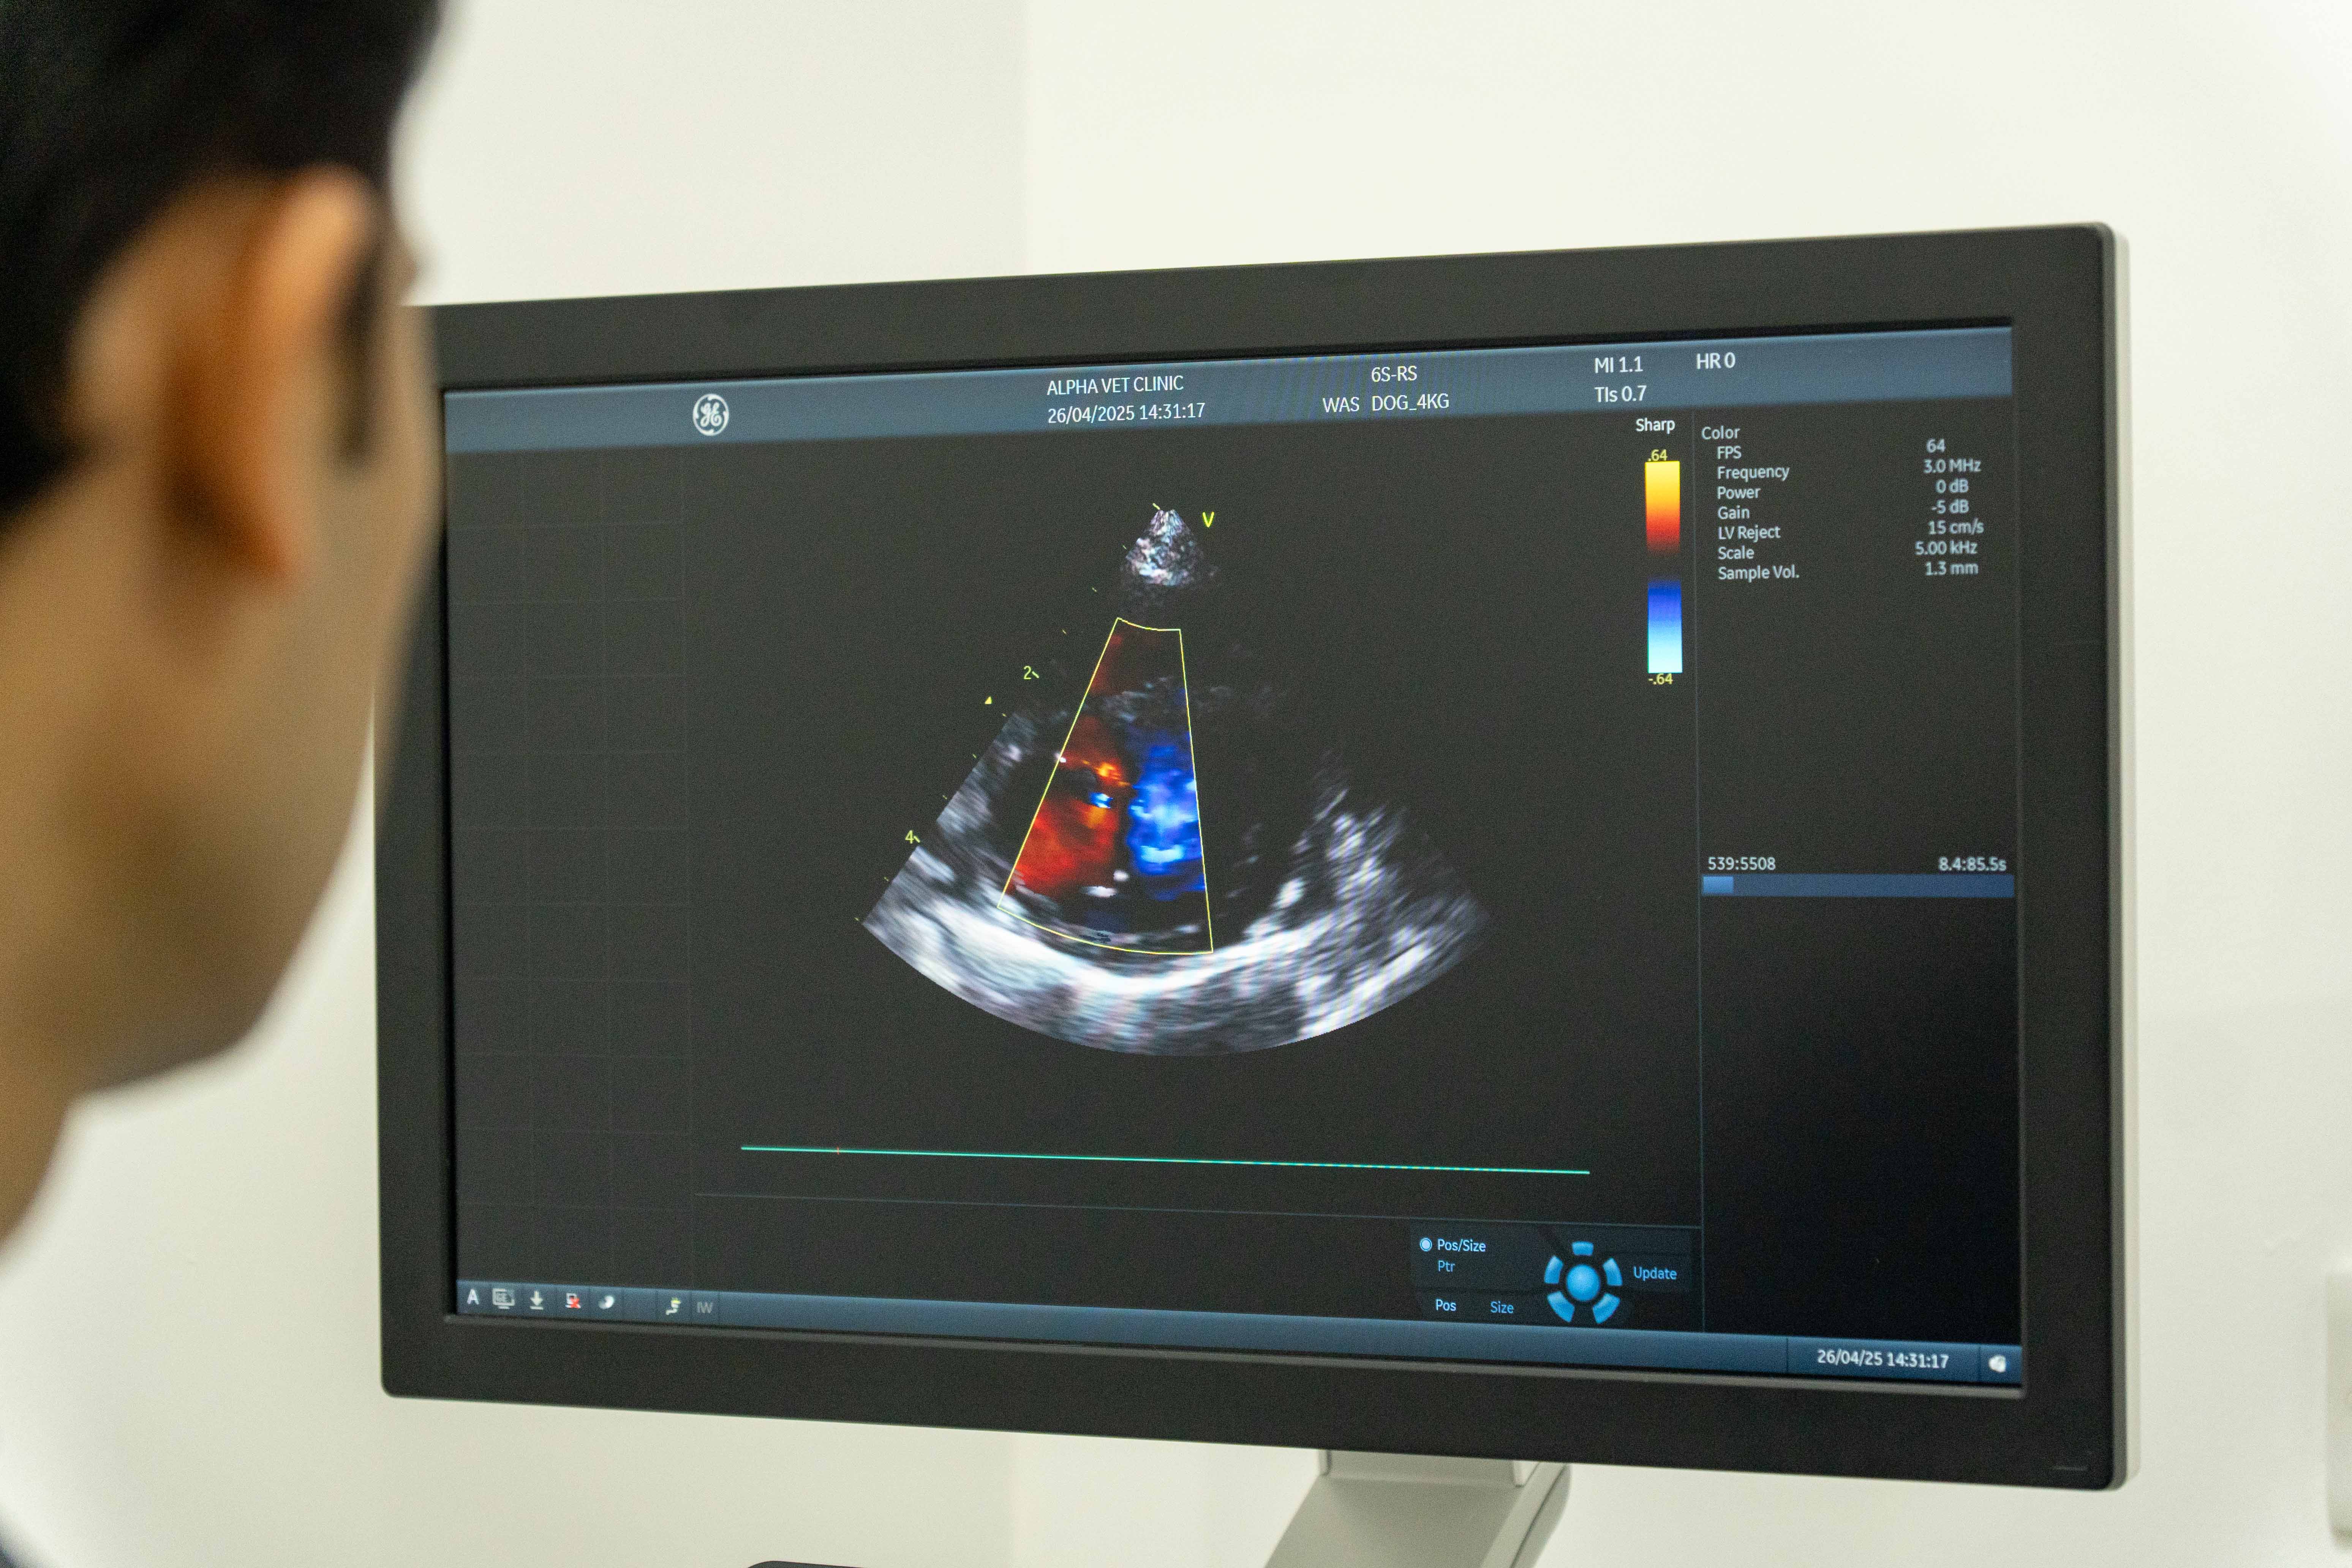

• Echocardiography (Ultrasound of the Heart): An echocardiogram provides a detailed view of the heart’s structure and function. This test is essential for diagnosing: ○ Valve disease (e.g., mitral valve insufficiency) ○ Cardiomyopathies (e.g., dilated or hypertrophic cardiomyopathy) ○ Congenital heart defects ○ Heart wall motion abnormalities

Our ultrasound technology enables real-time, dynamic imaging, allowing us to visualize structures inside your pet’s body and make informed decisions about their care.